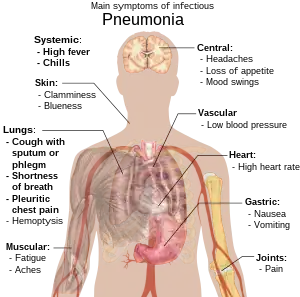

Folk med smittefarlig lungebetændelse har tit produktiv hoste (de hoster slim op), feber efterfulgt af ryste- og kuldeanfald, stakåndethed, skarpe eller stikkende brystsmerter, når de trækker vejret dybt og hurtig vejrtrækning.[9] Hos ældre patienter kan forvirring være det mest udtalte symptom.[9] Hos børn under fem er de typiske symptomer feber, hoste og hurtig eller besværet vejrtrækning.[10]

Feber er ikke et specifikt symptom, da det også forekommer ved mange andre almindelige sygdomme og måske ikke viser sig, hvis patienten har andre alvorlige sygdomme eller er underernæret.[10] Tit ses hoste heller ikke hos børn under to måneder. Flere alvorlige symptomer kan være: central cyanose (blålig farvning af huden), mindre tørst, rysteture, vedvarende opkastninger, meget svingende temperatur eller bevidsthedssløring.[10][11]

Lungebetændelser som følge af vira eller bakterier har som regel samme symptomer.[12] Nogle årsager forbindes med klassiske, men ikke-specifikke kliniske karakteristika. Lungebetændelse, der skyldes Legionella, kan give mavesmerter, diarre eller forvirring,[13] mens lungebetændelse, der skyldes Streptococcus pneumoniae, forbindes med rustfarvet opspyt,[14] og lungebetændelse, der skyldes Klebsiella-bakterier kan give blodigt opspyt.[8] Ophostning af blod fra luftvejene (hæmoptyse) kan også skyldes tuberkulose, gramnegativ lungebetændelse og lungeabscesser (bylder) og hyppigere akut bronkitis.[11] Af Mycoplasma-bakterier forårsaget lungebetændelse kan føre til hævede lymfeknuder på halsen, ledsmerter eller mellemørebetændelse.[11] Viral lungebetændelse viser sig oftere ved hvæsende vejrtrækning end bakteriel lungebetændelse.[12]